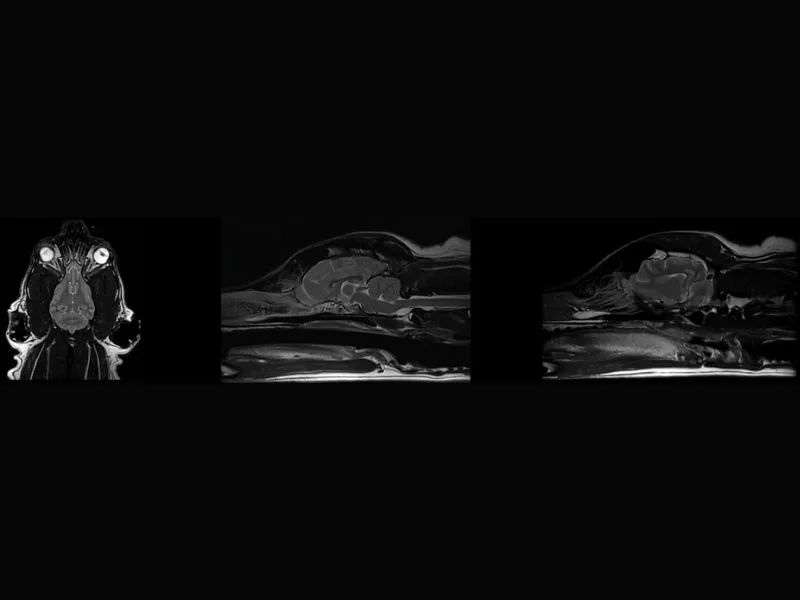

G-scan equine – FSE T2 Sagittal Splancnochranium

G-scan equine – FSE T2 Transversal Splanchnocranium